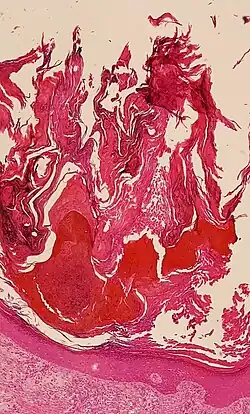

![]() Histologic image of human epidermis in thick skin | |

The stratum corneum (Latin for 'horny layer') is the outermost layer of the epidermis of the skin. Consisting of dead tissue, it protects underlying tissue from infection, dehydration, chemicals, and mechanical stress. It is composed of 15 to 20 layers of flattened cells with no nuclei or cell organelles.

The human stratum corneum comprises several levels of flattened corneocytes that are divided into two layers: the stratum disjunctum and stratum compactum. The stratum disjunctum is the uppermost and loosest layer of skin. The skin's protective acid mantle and lipid barrier sit on top of the stratum disjunctum.[5] The stratum compactum is the comparatively deeper, more compacted and more cohesive part of the stratum corneum.[6] The corneocytes of the stratum disjunctum are larger, more rigid and more hydrophobic than those of the stratum compactum.[7]

The thickness of the stratum corneum varies throughout the body. In the palms of the hands and the soles of the feet (sometimes knees, elbows,[9] and knuckles) this layer is stabilized and built by the stratum lucidum (clear phase) which allows the cells to concentrate keratin and toughen them before they rise into a typically thicker, more cohesive stratum corneum. The mechanical stress of heavy structural strain causes this stratum lucidum phase in these regions which require additional protection in order to grasp objects, resist abrasion or impact, and avoid injury. In general, the stratum corneum contains 15 to 20 layers of corneocytes. The stratum corneum has a thickness of between 10 and 40 μm.